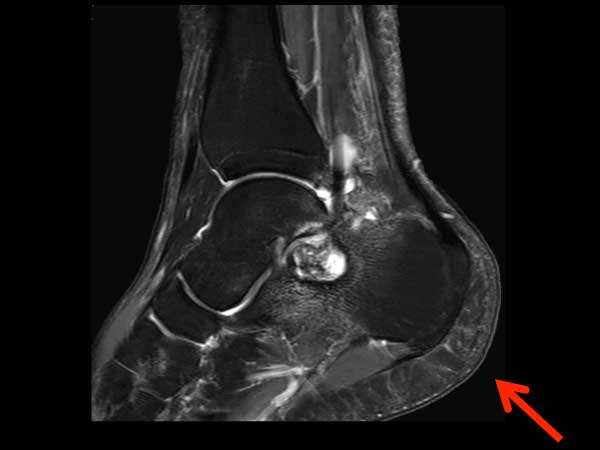

Sagittal T2w mDIXON